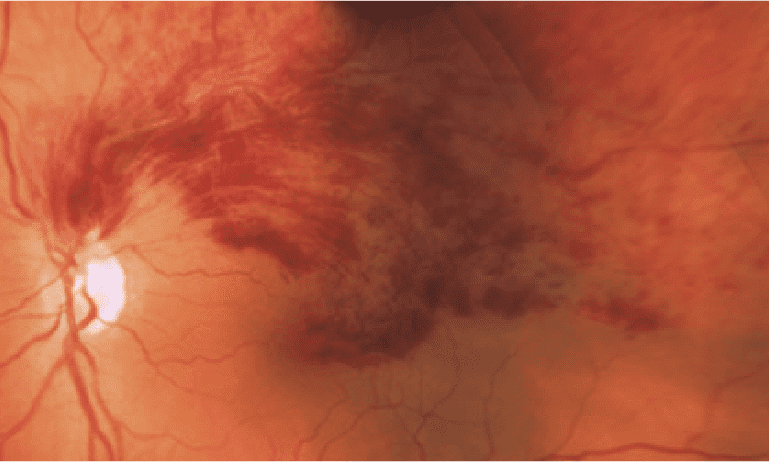

Oclusión de la vena central de la retina

Se obstruye la vena central de la retina.

El paciente percibe borrosidad o pérdida repentina de la visión que empeora con el paso de los días de forma indolora. Existen casos en los que esta pérdida de visión no es gradual sino de forma casi inmediata.

● Si la vena obstruida es la vena central de la retina, más severa será la pérdida de la visión.

Para diagnosticar una oclusión ocular es necesario realizar un completo examen oftalmológico para evaluar el fondo de ojo. Para ello, es imprescinible la realización de una tomografía de coherencia óptica (OCT) de alta resolución en todos los casos, así como de una angiografía con fluoresceína en ocasiones.

Con todas estas pruebas, el oftalmológo podrá ver la presencia de edema en la retina y/o hemorragias provocadas. Un especialista en diagnóstico por imagen de las enfermedades de la retina debe individualizar cada caso en función de los signos que aparezcan en dichas pruebas para poder ofrecer un pronóstico visual certero y planificar el tratamiento.